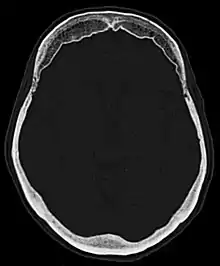

Hyperostosis frontalis at CT